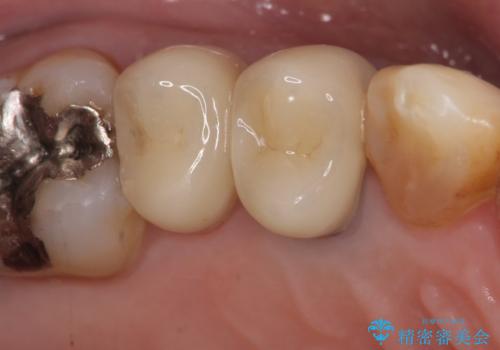

再根管治療後、オールセラミッククラウンによる補綴を行いました。

右上5も虫歯があったためオールセラミッククラウンによる補綴を行っております。

今回用いたオールセラミッククラウンはジルコニアフレームという白い素材の上にセラミックを盛っているため、審美性が非常に高いのが特徴です。

また、ジルコニアは人工ダイヤモンドの材料にも使われているほど高い強度を持っており、そのためオールセラミッククラウンは審美性だけでなく、奥歯やブリッジの補綴も可能とするクラウンです。